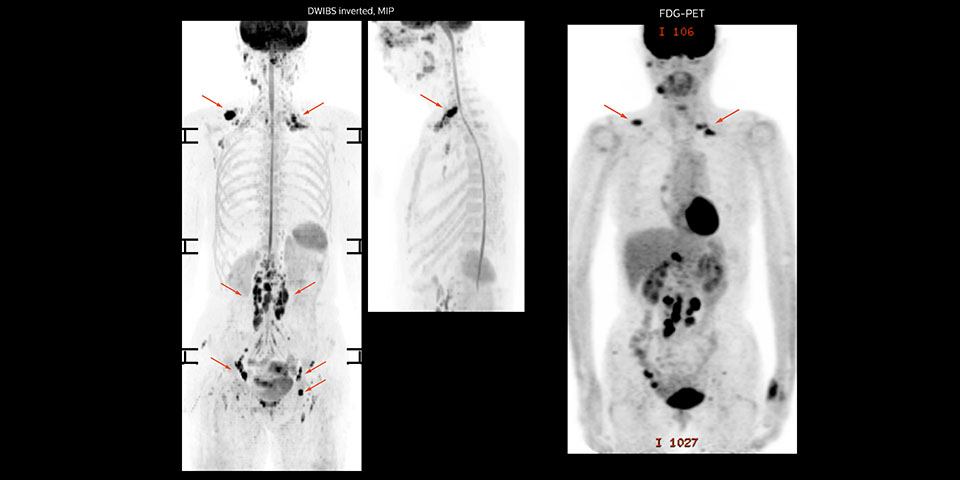

Whole body diffusion

A 61-year-old female with a malignant lymphoma underwent an MRI exam with whole body diffusion weighted imaging (DWIBS) as well as PET. On the images shown, the resolution of DWIBS is better than PET, which allows visualization of the small pelvic lesions and almost no distortion is seen in the neck area.